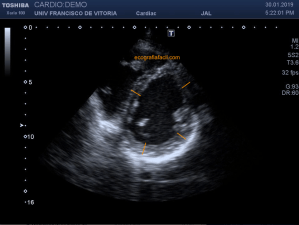

139. Ecocardiografía. Estudio Paraesternal Eje Largo.

141. Mediciones de los planos paraesternales.

142. Ecocardiografía.Plano Apical 4 cámaras